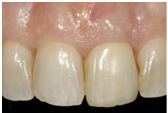

由於植體設計(macro- and micro-)與補綴組件的改良, 再加上人體臨床研究的實據, 前牙區的植牙已由早期兩階段翻瓣手術, 演進成一階段的手術(在條件允許下), 同時當臨床條件許可下, 有機會採用不翻瓣, 並合併在同一次門診中完成立即性臨時牙套的成功治療.

目前前牙立即植牙的挑戰, 已不是骨整合的達成而是如何使創傷更小, 時間更有效率, 並且可預期的達成美觀的臨床結果; 這和以下綜合因素相關:

此篇文章將詳細說明, 當遇到前牙需拔牙, 而齒槽窩屬type 1 (軟硬組織皆理想) 時, 如何安排一個適當的手術與補綴流程, 去保留住自然牙時,原本具備的美觀形態. 避免或減少拔牙後必然形成的bone remodeling,

文章所說的雙區域指的是"軟組織區"與"硬組織區";

-軟組織區 (Fig 1,2)是指"植體與支台交界以上的區域" , 這個區域的組織若型態改變或變薄, 則內部的abutment將會透出顏色使組織變色 (abutment shine-through effect)

-硬組織區 (Fig 3,4)則是指"植體與支台交界以下的區域" , 這個區域的組織若因骨嵴塌陷造成型態改變或變薄, 則內部的implant body也可能會透出顏色使組織變色 (implant body shine-through effect)

(Fig 1,2)

(Fig 3,4)